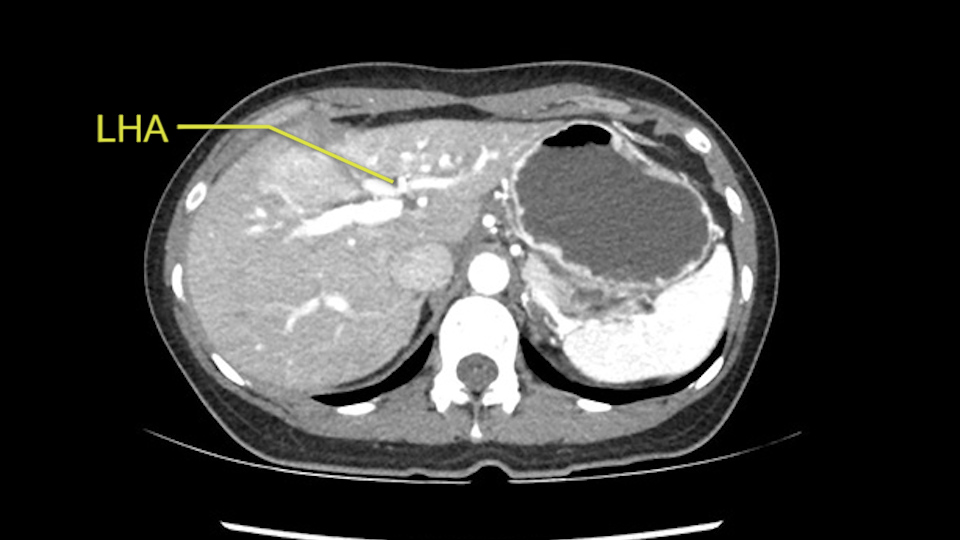

Anatomically, to plan for a left lateral segmentectomy, it’s relatively easy as far as liver surgery goes. I know that I'm going to be looking for the left hepatic vein which will be divided at some point either towards the end at the back near the vena cava or through the middle of the left lateral segment.

Inflow is not usually an issue except if there are as a replaced or aberrant left hepatic artery. In which case you’d be careful when you mobilize the left lateral segment.

So I have to say that I would do this open, not laparoscopically because of the size of the tumor itself. Upper abdominal incision. Almost certainly, we’d be able to flip this very exophytic lesion up. Intraoperative ultrasound will show the relationship of the tumor and the left portal vein but the dissection at the base of the liver, as I look at things here, I can see the left hepatic artery which sneaks up to the left of the portal vein, should be out of harm’s way so I can take the Segment 2-3 left hepatic artery. The left portal vein is somewhat compressed. But by the time you pull the liver up a bit, you’ll be able to pull that left portal vein out to length and get a good margin on it.

The second is the left hepatic artery. The tumor is displacing the arterial system. So one of the important points which we need to see intraoperatively is to identify and preserve the right artery very carefully and identify the left hepatic artery for ligation.

So in planning for this operation, as I look at the scans, I first visualize the arterial phase and I can see that there’s are a lot of big feeding arteries to this large tumor. Likely all the right side vessels feeding the right side of the liver: right hepatic artery and likely the Segment 4 artery are spared from the tumor. It’s likely the left hepatic artery is ramificating and giving feeding arteries to this tumor. It certainly looks like a large mass that its compressing other structures like the cava, the pancreas, the stomach; but I think there’s a plane and we can see that better in the venous phase. There’s a plane of separation between the gallbladder, the pancreas, the cava, that this tumor is abrupting but likely not invading. Usually, these masses actually don’t invade at that level and basically are pushing the tissues and once you open, you’re able to separate the tumor. Sometimes there’s some adhesions but you can actually separate and there’s usually no invasion.